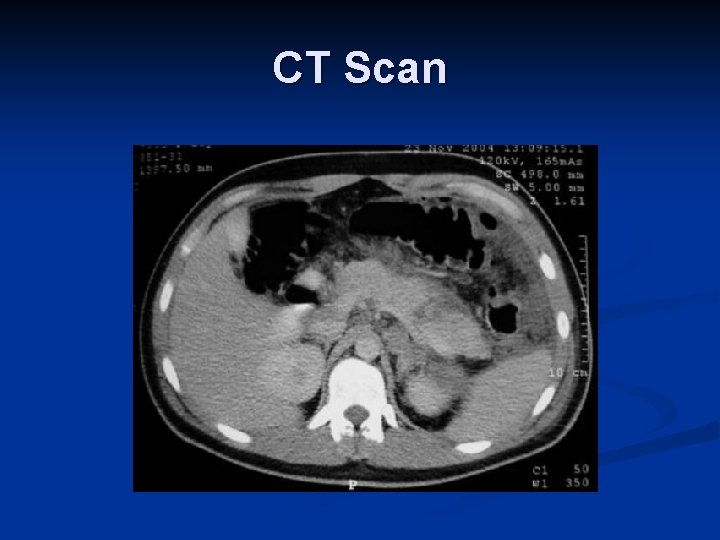

Imaging in Blunt Abdominal Trauma – CT Scan n Sensitivity: n Solid organ injury: 97% [II, III] n Identify Contrast extravasation n Guide Operative vs. Non-operative management n Enteric injury: 64 – 94% [III] n Diaphragmatic injury: 61% [III] n Pancreatic injury: 30% [III]

CT Scan

CT Scan

CT Scan

Learning Points Case #2 CT scan is helpful for decision making in a stable patient n Poor detection of hollow viscus, pancreatic and diaphragmatic injury n Be worried of free fluid in abdomen n Repeat CT Scan and close clinical observation n